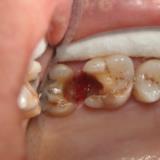

Immediate Implant Placement

A molar either maxillary or mandible always represents a little difficult and tricky scenario for implant placement immediately after extarction. There is always some sacrifice for the location, angle etc. however you save some time and patients go through a procedure once and it is a reliable method of replacing a tooth, when feasible. Dental implant is always a compromised replacement and a tooth restored with immediate placement is not any different.